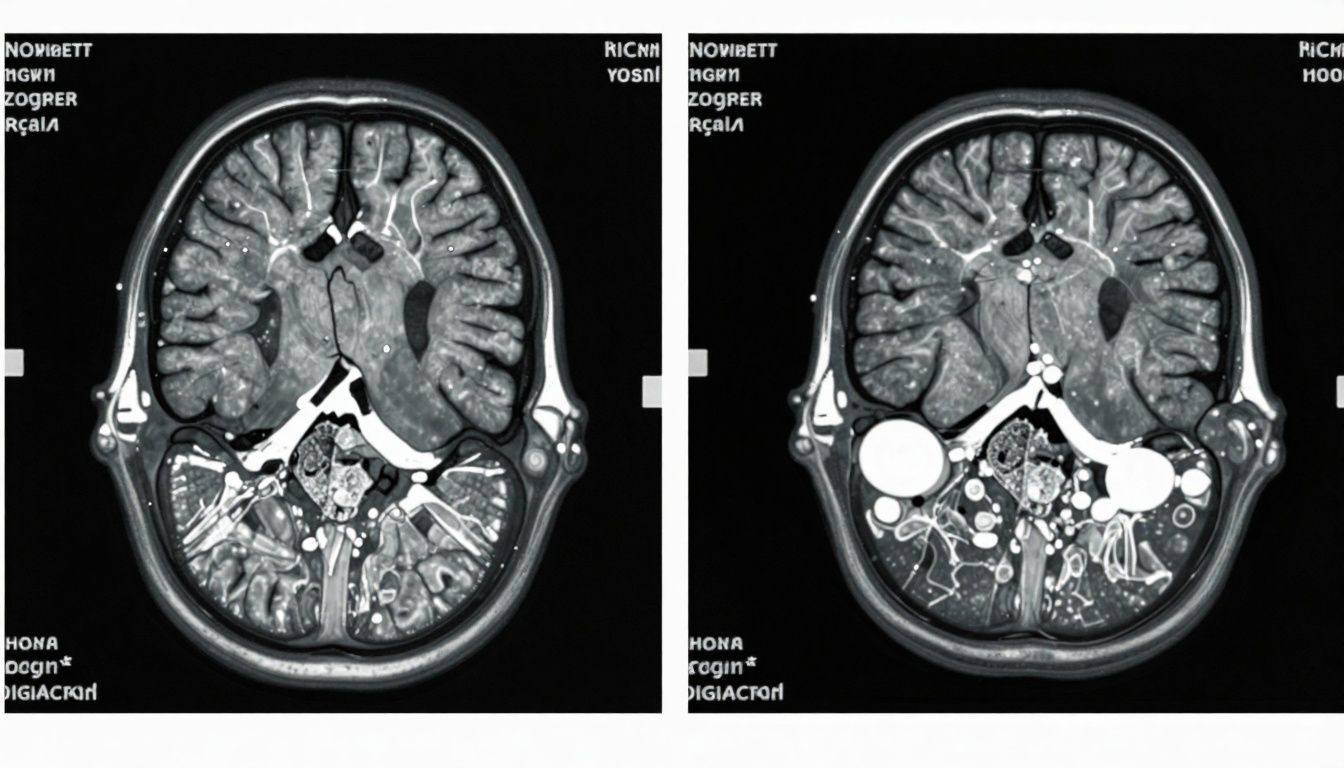

Addressing Individual Variability

Not all individuals experience cognitive decline in aging at the same rate. Inter-individual variability is influenced by genetics, life experience, educational attainment, co-morbid conditions, and access to medical care.

- Precision medicine is likely to tailor future interventions, including targeted use of peptides for neuroprotection or disease-modifying treatments.

- Assessment tools such as genetic risk scoring and advanced imaging might soon guide more personalized prevention strategies.